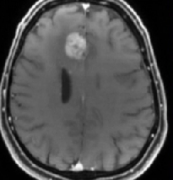

胶质母细胞瘤是成人中较常见和较恶性的原发性脑肿瘤,每位患者的生命损失超过20年。GTR的定义是在手术后72小时内,在增强的T1加权术后磁共振成像扫描上完全切除增强的肿瘤。然而...

多形性胶质母细胞瘤(GBM)是成人中常见的具侵袭性的原发性脑肿瘤。为巩固手术效果通常需要术后放化疗,恶性脑胶质瘤多长时间放化疗一个周期...